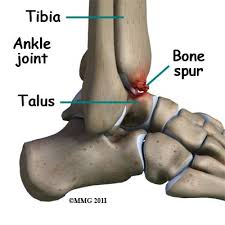

Medial Malleolus Bone Spur - Anterior Ankle Impingement Dynamic Physio Therapy Naples Fl Physical Therapy : Both the smooth surface on the inside of the medial malleolus and the.. Bone spurs are bony projections that develop along bone edges. When the tibial tuberosity separates from the body of the tibia. What medical devices treat bone spurs? Sometimes, a medial malleolus fracture may result in impaction of the ankle joint, which is when force drives one bone into another. Medial malleolus stock photos & medial malleolus stock.

Medial malleolus and talus make up the medial side. Surgery on the medial malleoli can improve the chances of successful healing and allow the person to resume normal movement sooner. How do health care professionals diagnose bone spurs? Corns and calluses also often form over the site of a. The medial malleolus is a bony non articular enlargement of the distal part of tibia, medially to the cochlea. The medial malleolus is an anatomical region of the tibia bone, which is the larger of the two lower leg bones. Each leg is supported by two bones, the tibia on the inner side (medial) of the leg and the fibula on the outer side (lateral) of the leg. Now my doctor call me to his clinic with a new xray on 15th may 2017.

But a medial malleolus fracture is more often part of a compound injury involving one or both of the other ankle parts. Corns and calluses also often form over the site of a. Bone spur removal is not a minor procedure. The medial malleolus is a bony non articular enlargement of the distal part of tibia, medially to the cochlea. The tibia (shin bone) is the medial bone of the leg and is larger than the fibula, with which it is paired (figure 3). Small amount of distal achilles. If talar rotation continues, the medial malleolus is avulsed and the deltoid ligament may rupture. Tibiotalar joint space make up the top. Both the smooth surface on the inside of the medial malleolus and the. Marked soft tissue swelling over the lateral malleolus with a small bony fragment and increased lucency at the tip which. What specialists treat bone spurs? How do health care professionals diagnose bone spurs? The relationship between spur formation, the medial tubercle of the calcaneus and intrinsic heel musculature results in a constant pulling effect on the plantar fascia resulting in an inflammatory.

While the name suggests that the growths are sharp or jagged, spurs are common symptoms of bone spurs include swelling, pain, and tearing in your muscles and tendons.

Explore the five types of breaks and when surgery may be required by your doctor. Bone spurs are abnormal spiking outgrowth of the bone around the edge or border of the bone. Knowledge of this is useful for massage therapists and other clinical professionals. Case contributed by dr henry knipe ◉ ◈. If talar rotation continues, the medial malleolus is avulsed and the deltoid ligament may rupture. Marked soft tissue swelling over the lateral malleolus with a small bony fragment and increased lucency at the tip which. Spurs may be observed over shaft or end of the bone involved in joint formation. What are treatment options for a bone spur?